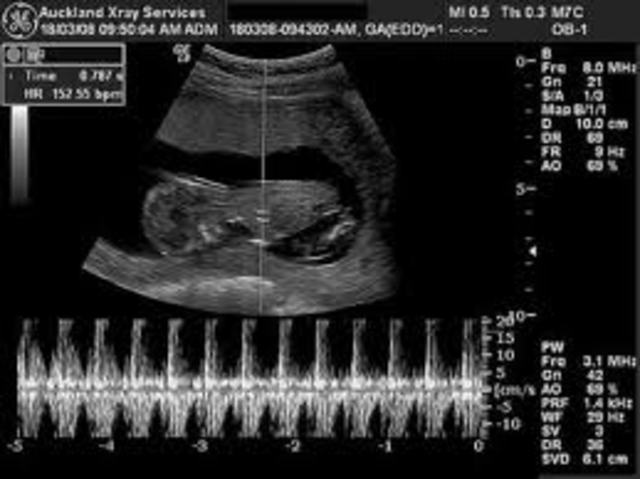

• Prenatal #2 Heartbeat

Prenatal #2 Heartbeat

Physical Development

The baby's heart is developed and begins to beat! This usually happens at around 6 weeks.

Image from fetalheartbeat.org